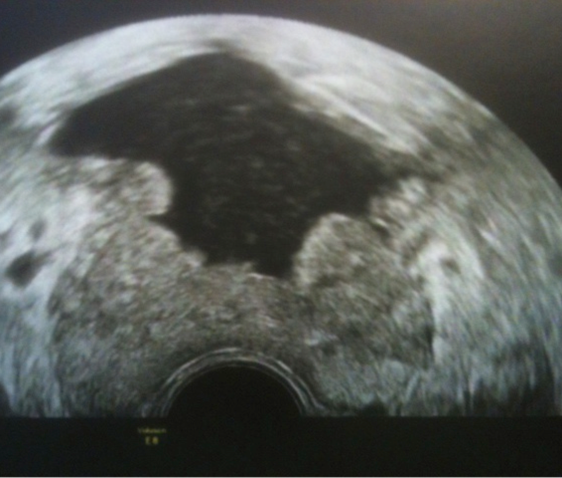

Un adénome de la prostate de moyen volume avec étude doppler portant sur la partie centrale adénomateuse.

Le même patient après énucléation au laser Holmium de l’adénome central: la prostate est réduite à la zone périphérique avec une vaste loge centrale d’énucléation.